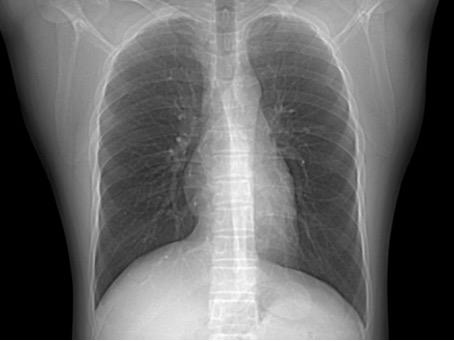

正常胸部正位片